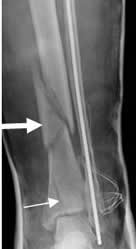

Fig 47. Fractura diastasada.

A: y B: Rx lateral. Fracturas conminutas, rotadas y diastasadas en las diáfisis femorales.